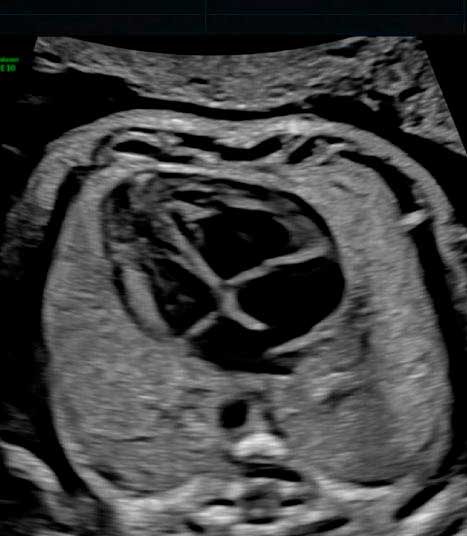

Se recomienda un examen especializado del corazón fetal para:

• Las mujeres con antecedentes familiares de anomalías cardiacas congénitas, las que tienen diabetes mellitus y aquellas que toman fármacos antiepilépticos.

• Fetos con sospecha de defecto cardíaco y aquellos con mayor translucencia nucal o ciertas anomalías no cardíacas detectadas durante las exploraciones de rutina.

INCLUYE:

– Ecografía en HD Live Resolution (5D/7D).

– Estudio Doppler.

– Informe e imágenes impresas en b/n.

– Una foto postal a color.

– Video e Imagénes de la ecografía en MP4 y JPG enviados a su correo electrónico via nuestra cuenta corporativa en WeTransfer.

– Estacionamiento incluido.

– Explicación de los hallazgos ecográficos.

Se recomienda un examen especializado del corazón fetal para:

• Las mujeres con antecedentes familiares de anomalías cardiacas congénitas, las que tienen diabetes mellitus y aquellas que toman fármacos antiepilépticos.

• Fetos con sospecha de defecto cardíaco y aquellos con mayor translucencia nucal o ciertas anomalías no cardíacas detectadas durante las exploraciones de rutina.

INCLUYE:

– Ecografía en HD Live Resolution (5D/7D).

– Estudio Doppler.

– Informe e imágenes impresas en b/n.

– Una foto postal a color.

– Video e Imagénes de la ecografía en MP4 y JPG enviados a su correo electrónico via nuestra cuenta corporativa en WeTransfer.

– Estacionamiento incluido.

– Explicación de los hallazgos ecográficos.

Dr. Enrique Gil G.